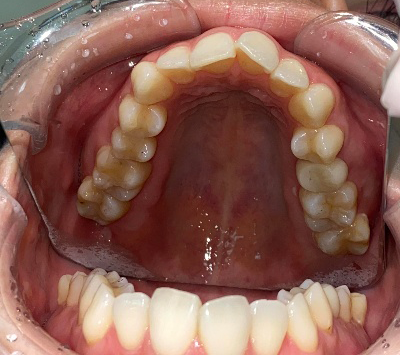

来院時の歯並び写真

上下前歯の歯並びがガタガタしているのが気になる、きれいにしたいとのご希望で来院されました。